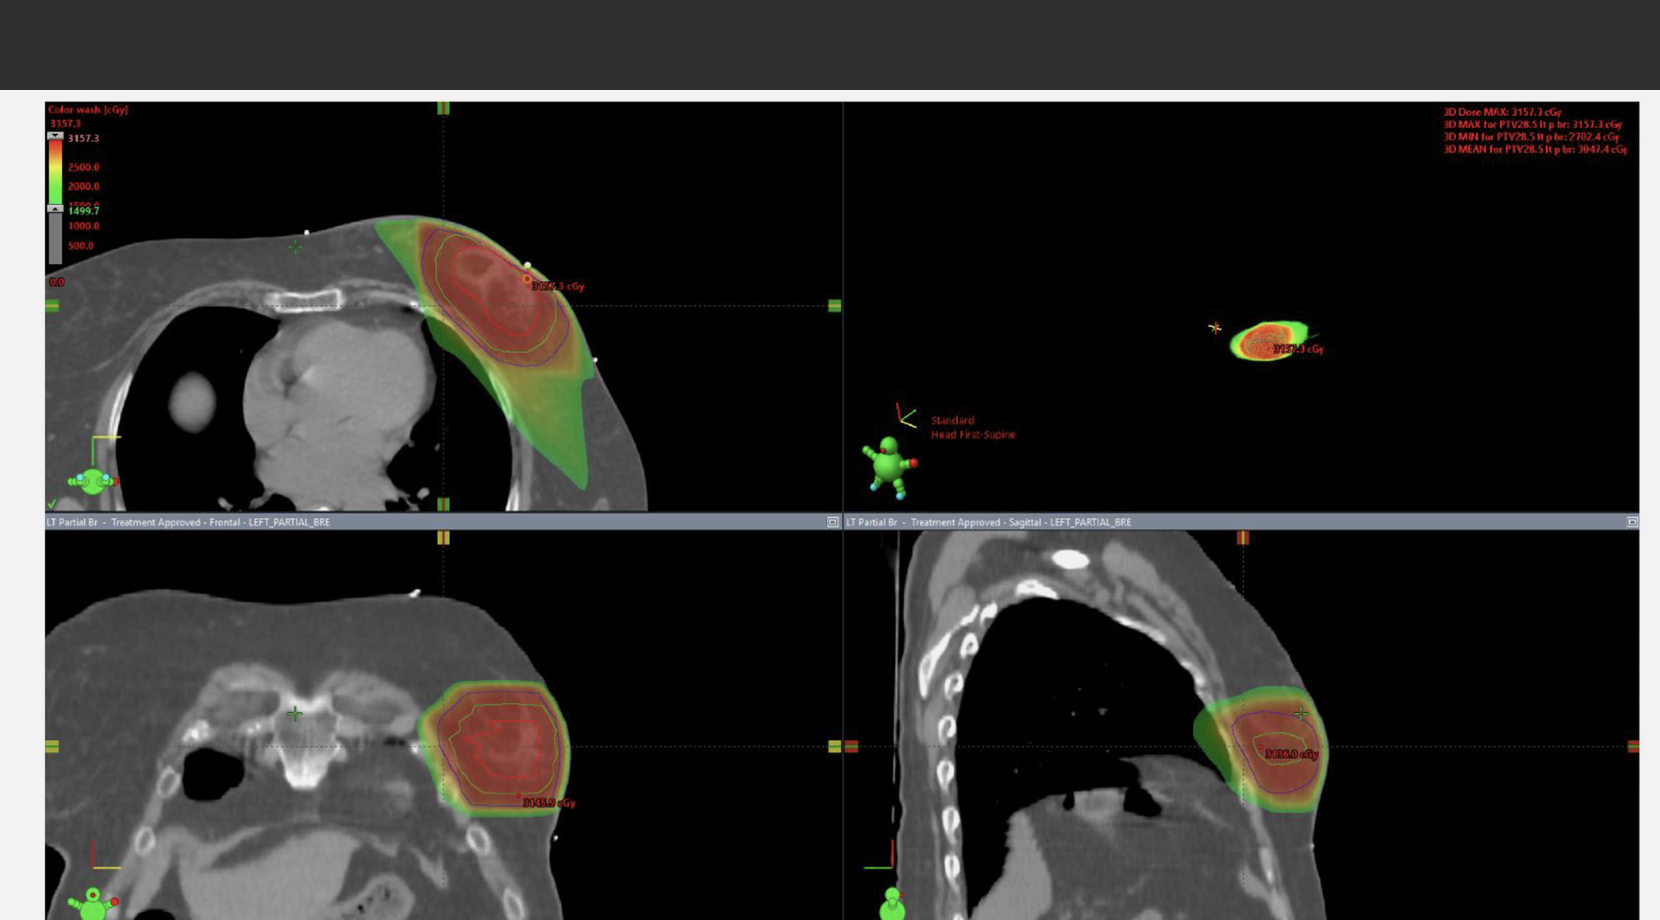

A Radiation dose distribution in a patient treated with lumpectomy with oncoplastic reconstruction

(A) Radiation dose distribution in a patient treated with lumpectomy with oncoplastic reconstruction. The tumor bed is contoured in red, the PTV30 in cyan, and the PTV28.5 in dark blue. (B) Bilateral breast MRI with contrast demonstrates subareolar enhancing mass to assist with target delineation despite oncoplastic reconstruction.